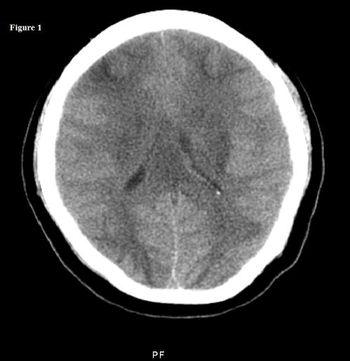

The patient's medical history was notable for hypertension, diabetes mellitus, and seizure disorder. Here, find images and lab results; then select a diagnosis.

A young woman was admitted at 36 weeks' gestation with severe preeclampsia. During delivery, she experienced generalized seizures. She remained postictal throughout the normal vaginal birth.

Bilateral strokes of the corpus callosum are uncommon because of the rich blood supply of this structure from three main arterial systems.